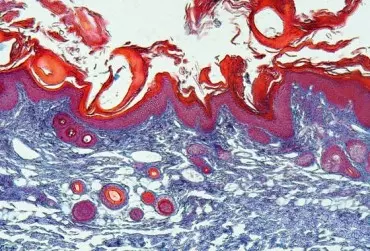

Skórę niemowląt i dzieci charakteryzują liczne odrębności rozwojowe, co przekłada się na wyraźniej niekorzystny wpływ promieniowania słonecznego w porównaniu do osób dorosłych. Okres dzieciństwa jest czasem szczególnej wrażliwości dla wzrostu ryzyka zachorowania na nowotwory skóry w późniejszych etapach życia, a wdrożenie odpowiednich działań edukacyjnych dzieci i ich rodziców staje się szczególnie istotne. W przypadku dzieci najistotniejszą strategią fotoprotekcyjną wydaje się modyfikacja postępowania, związana z pozostawaniem w cieniu, noszeniem odpowiedniej odzieży, w tym czapek i kapeluszy oraz okularów ochronnych. Są to zarazem najlepsze i najtańsze metody ochrony przeciwsłonecznej. Jednakże szeroko pojęte działania edukacyjne oraz profilaktyczne w zakresie fotoprotekcji nie są wystarczające w przypadku dodatniego wywiadu osobniczego lub rodzinnego w kierunku nowotworów skóry, głównie czerniaka. Co istotne, wykazano, że regularne stosowanie fotoprotekcji u dzieci może ograniczyć rozwój znamion melanocytowych. W niniejszym artykule omówiono zasady fotoprotekcji u niemowląt i dzieci oraz działania profilaktyczne w przypadku znamion skórnych u pacjentów pediatrycznych. Warto podkreślić, że u niemowląt poniżej 6. m.ż., w przypadku braku możliwości pozostawania w cieniu i/lub dostępu do odzieży ochronnej, należy nakładać kremy z co najmniej SPF 15 na małe powierzchnie ciała, na przykład policzki, grzbiety rąk. U dzieci powyżej 6. m.ż. zaleca się stosowanie wodoodpornych preparatów z SPF co najmniej 30, najlepiej z przewagą filtrów fizycznych, takich jak tlenek cynku lub dwutlenek tytanu, których dotyczy mniejsze ryzyko miejscowego podrażnienia skóry. Preparaty należy aplikować na całą skórę, ze szczególną ostrożnością w obrębie okolic oczu.